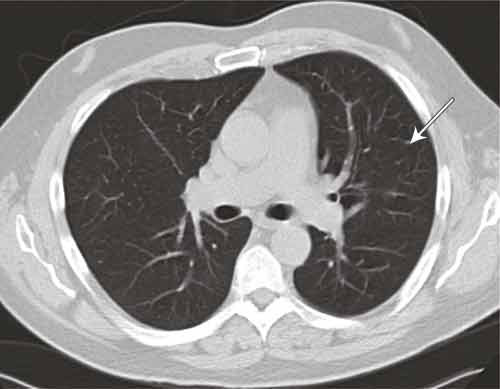

The patient was given a thorough examination. Differential diagnostic possibilities as mentioned in the literature (Fig. 3) were eliminated, with the exception of Wegener’s granulomatosis, which could not be excluded with certainty. Further studies were therefore focused on this. The sole positive finding was c-ANCA, which was weakly positive initially, but subsequently within the reference range. Blood tests were otherwise normal. No skin changes or heart or kidney affection were found. CT of the temporal bone showed fluid and soft tissue thickening in the middle ear and denser mastoid cells on the left side. CT of the sinuses showed a hypoplastic left maxillary sinus with thickening of the mucous membrane and an air-fluid level, but no granuloma. The conclusion of a biopsy of the respiratory mucous membrane was non-specific chronic infection, and no vasculitis or granuloma. CT of the thorax showed possible progression of one of the small non-specific nodular opacities found in the left upper lobe at the onset of the illness, but the change was not accessible for biopsy (Fig. 4).

Figure 4  CT thorax. Small, non-specific nodules in left upper lobe